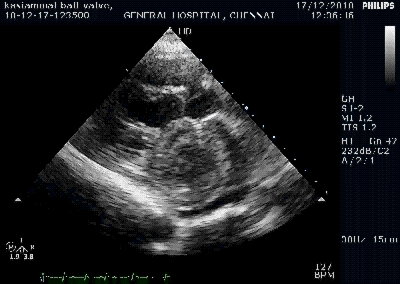

Mitral regurgitation is one of the most common lesion of rheumatic heart disease .Mechanism of MR in acute rheumatic fever is different from chronic rheumatic heart disease.

Chronic rheumatic heart disease

As the mitral valve gets progressively damaged any combination of MS or MR occur .The following mechanism are involved in the genesis of MR. (Pathology of Mitral stenosis is not discussed here)

- Chordal shortening, tethering , pulling , prevent proper co-optation

- Chordal lengthening

- Chordal disruption (Minor > Major )

- Prolapse of either AML or PML (Not both ,unlike myxamatous MVPS)

- Infective endocardits of leaflet

- Perforations of leaflet

- Annular dilatation